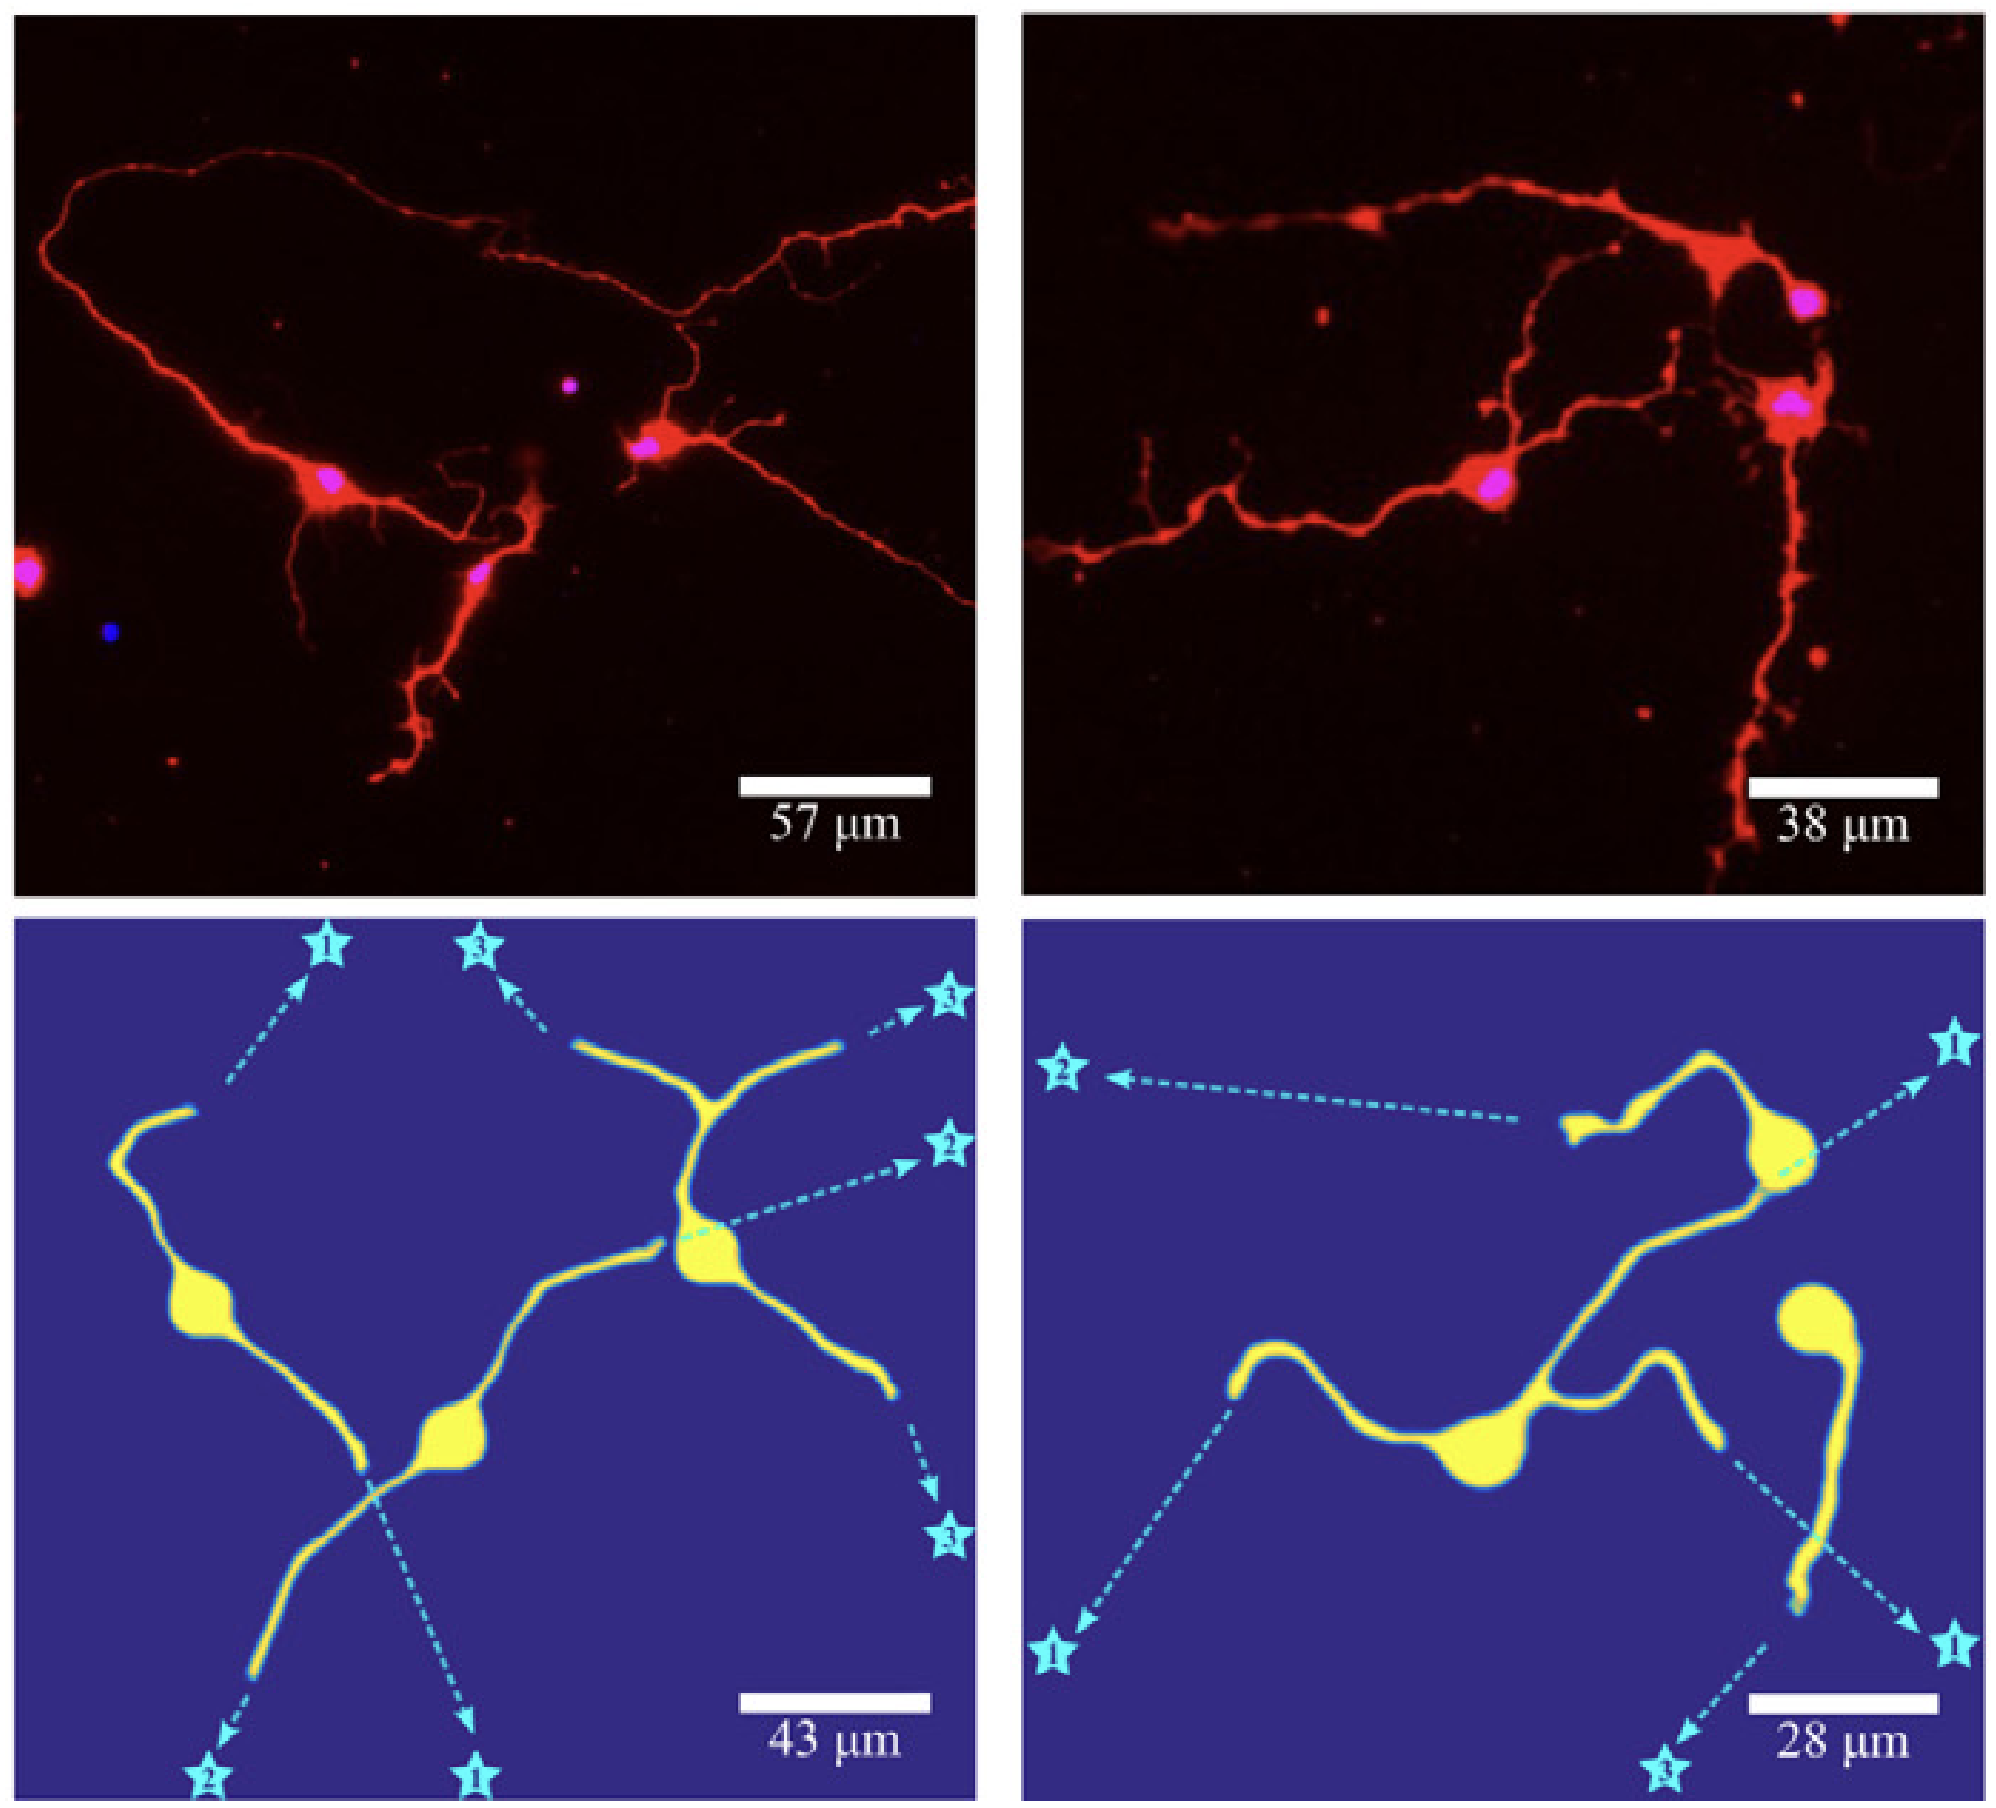

Novel High-order Algorithm on 3D Spline for Modeling Biological Neuron Growth

Custom C++ high performance algorithm for solving high-order nonlinear biophysics process on high-fidelity locally refined THB-splines

K. Qian, Y. J. Zhang. 3D neuron growth model using truncated hierarchical B-splines with multi-level local refinements.Computer Methods in Applied Mechanics and Engineering, 442, 118003, 2025.

Computational Modeling of Alzheimer's disease with Real Patients’ Neuron Cell

K. Qian, G. O. Suarez, T. Nambara, T. Kanekiyo, A. S. Liao, V. A. Webster-Wood, Y. J. Zhang. Neurodevelopmental Disorders Modeling using Isogeometric Analysis, Dynamic Domain Expansion and Local Refinement. Computer Methods in Applied Mechanics and Engineering, 433: 117534, 2025.